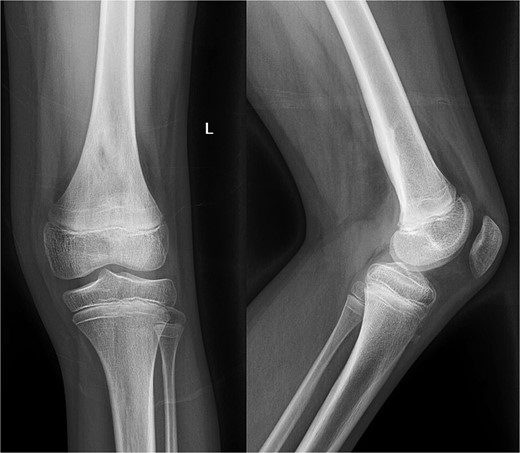

An 11-year-old healthy male presented with posterior left knee pain, which began 4 days after twisting his knee at a trampoline park. The pain progressed to a point where he was unable to bear weight on his left leg, and the knee became locked in flexion due to muscle spasms and pain. After three visits to outside facilities over 2 weeks, the patient finally received an orthopedic consultation. While radiographs were unremarkable, magnetic resonance imaging (MRI) revealed a large fluid collection posterior to the distal femur, suggestive of osteomyelitis, and Brodie’s abscess and associated local destruction of the posterior femoral cortex (Fig. 1a and c). The patient was then transferred to our institution for definitive management. Upon presentation, the patient was febrile (39°C) and nauseous with one episode of emesis. Physical examination revealed a tender and warmer left knee without open wounds. The patient denied a knowledge of current dental carries or a history of recent dental procedures and denied recent history of a streptococcal infection. Laboratory tests showed leukocytosis of 14 600 μl of white blood cells (WBC), elevated C-reactive protein (CRP) of 18 μg/ml (normal <0.3 μg/ml), and an elevated erythrocyte sedimentation rate (ESR) of 18 mm/h (normal <15 mm/h). A CT scan at our institution recapitulated findings suggestive of osteomyelitis, cortical destruction, and a noted thrombophlebitis of the popliteal vein (Fig. 1b).

Preoperative radiography, CT, and MRI. The radiographs were read as normal by the radiology, while the CT and MRI were read osteomyelitis with Brodie’s abscess involving the distal femoral epimetaphysis with destruction of the posterior cortex and associated 7 cm popliteal fossa abscess, along with a suspected nonocclusive septic thrombophlebitis of the popliteal vein mentioned in the report on the CT.